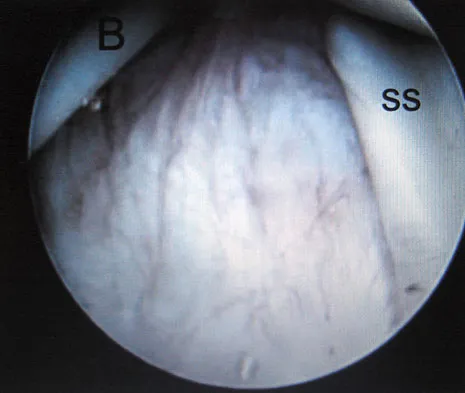

Question 92

A 15-year-old boy has had pain in the right shoulder for the past 3 months. He denies any history of trauma and has no constitutional symptoms. Examination reveals a large firm mass in the proximal arm. A radiograph and MRI scan are shown in Figures 27a and 27b. Biopsy specimens are shown in Figures 27c and 27d. Management should consist of

Explanation